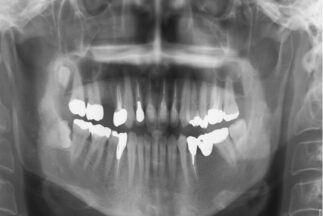

- After

| 治療内容 | 上顎右側5相当部へインプラント埋入と同時にチタンメッシュを用いて自家骨と骨補填材による骨増生術を行った |